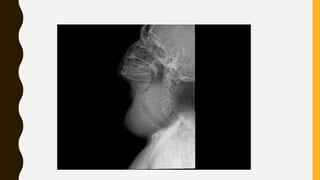

INVESTIGATIONS

• X-ray neck :AP & Lateral view

INVESTIGATIONS • Thyroid functiontests • Ultrasonography (USG) • Fine needle aspiration cytology (FNAC) • Complete blood picture (CBP) • X-ray neck :AP & Lateral view • CT scan : to look for retrosternal extension • Thyroid scan-contains radioactive I • Indirect laryngoscopy : to see vocal cord mobility